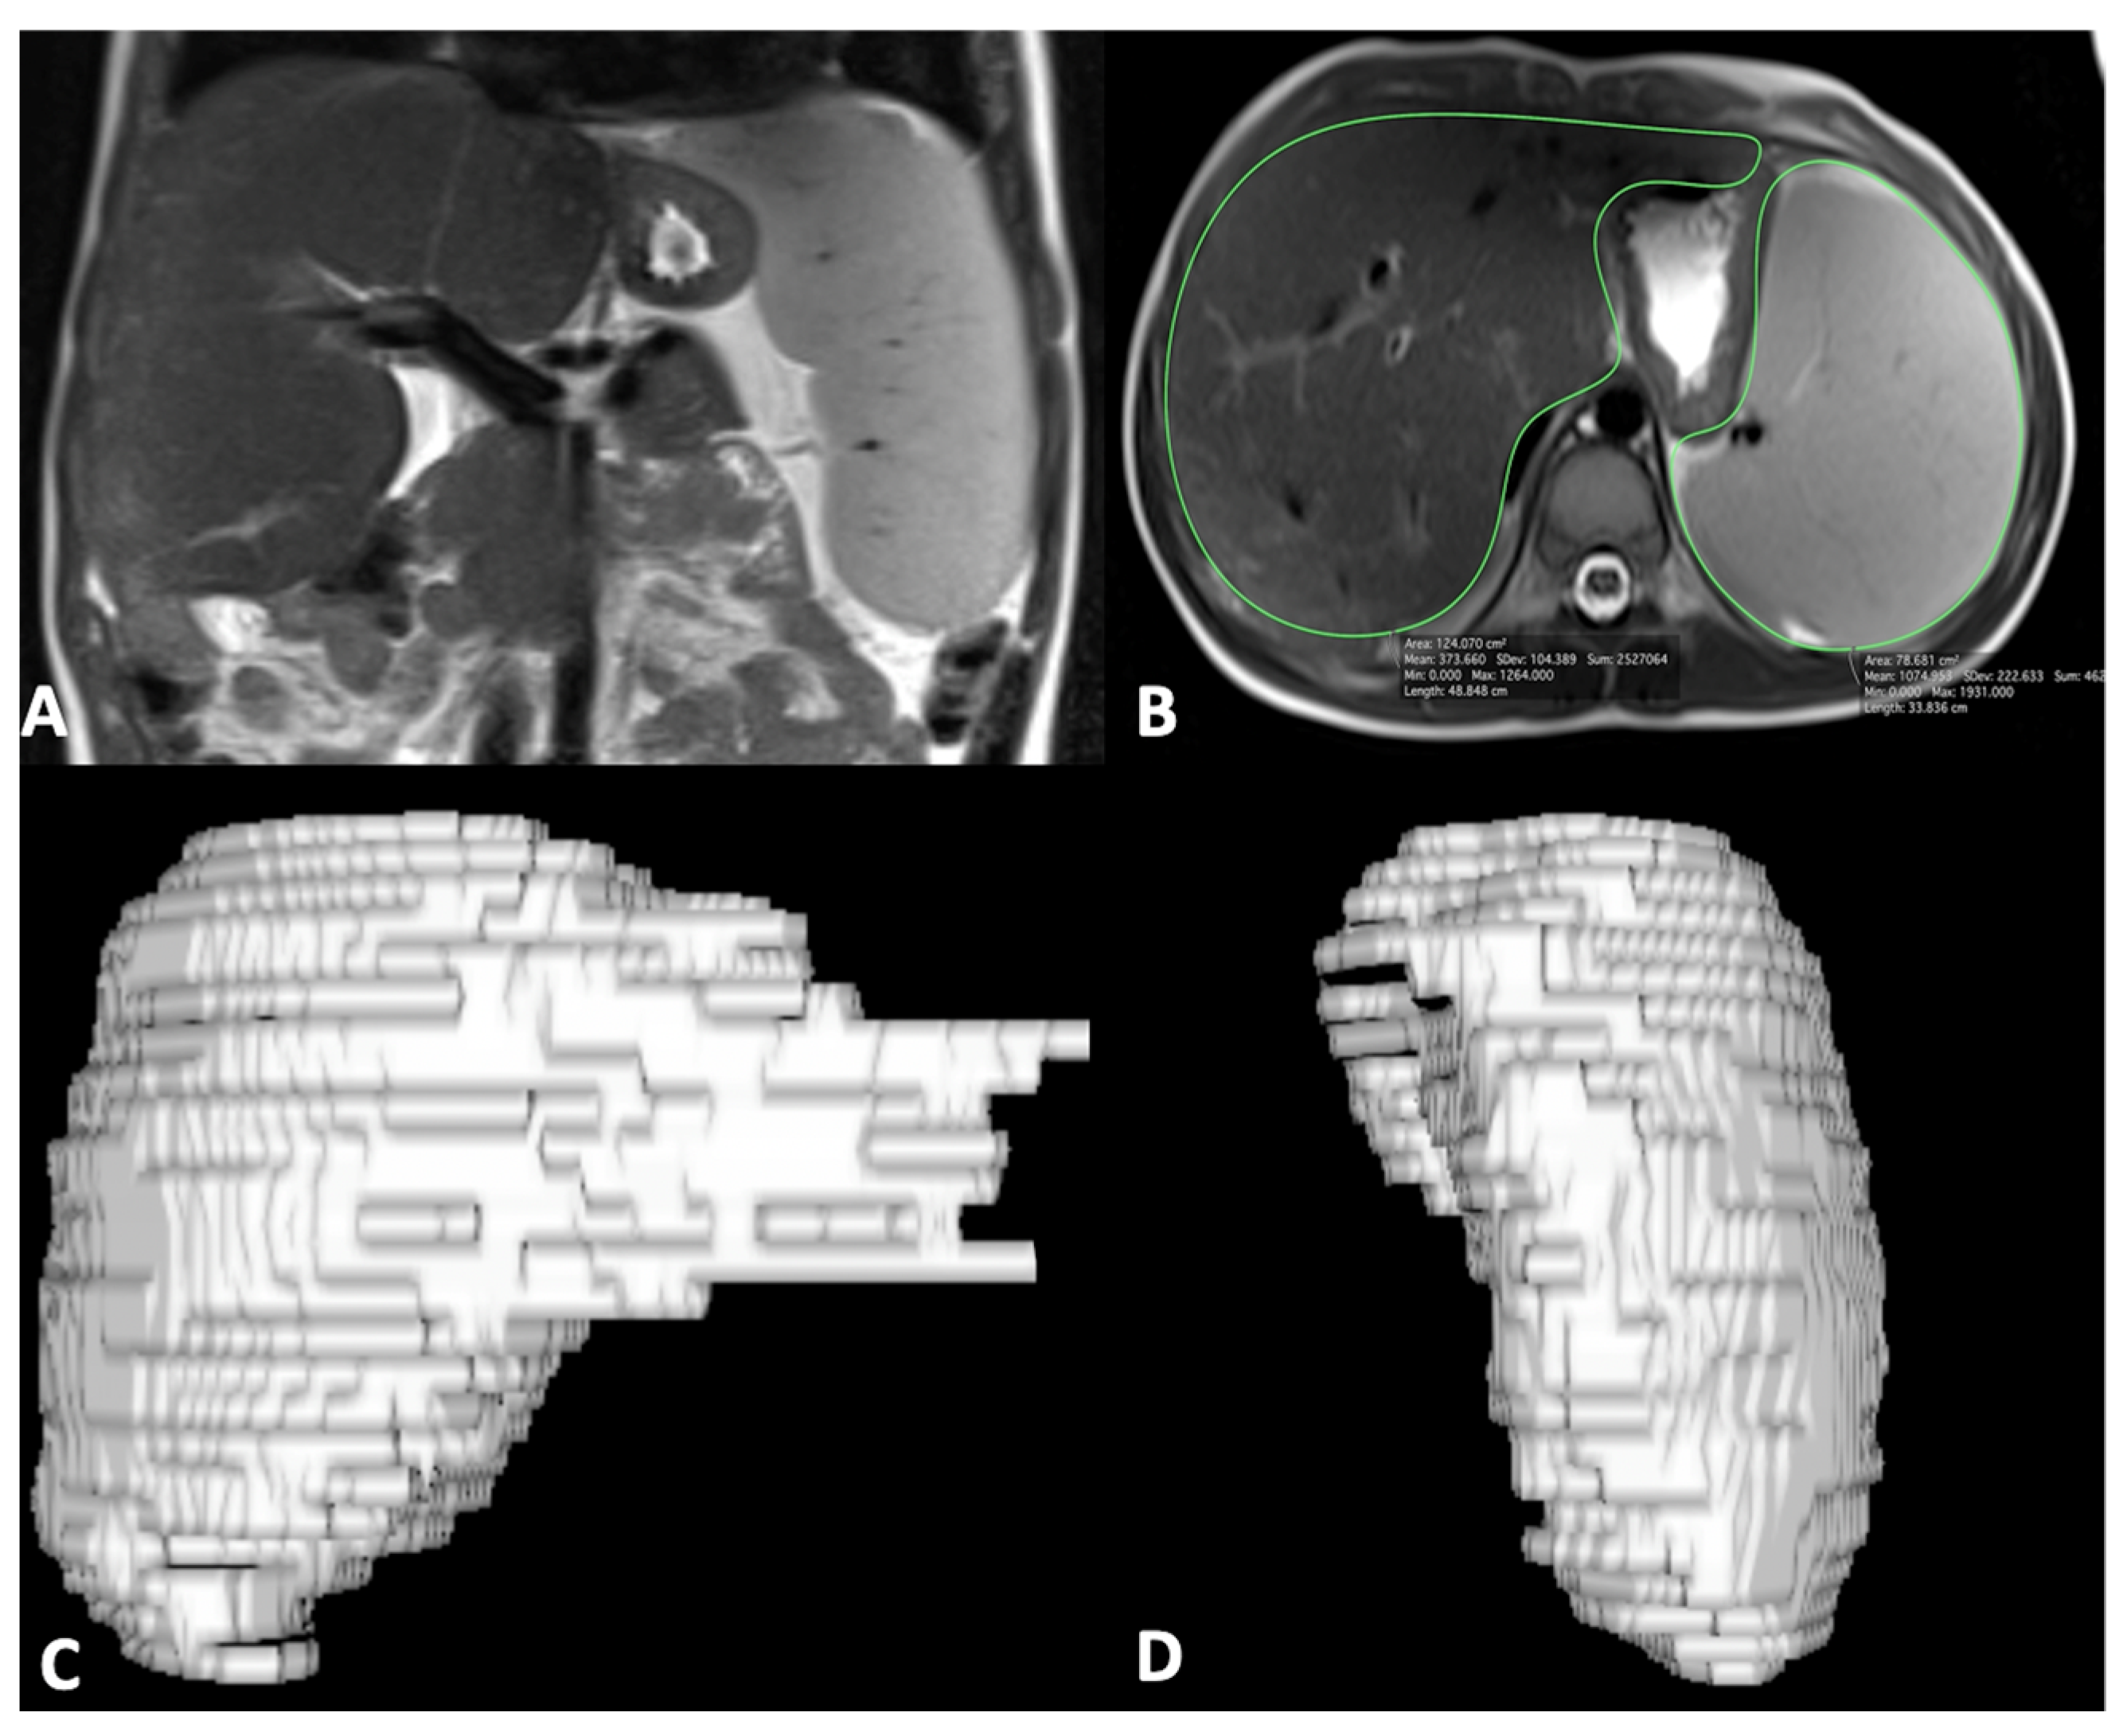

- Caruso, M.; Cuocolo, R.; Di Dato, F.; Mollica, C.; Vallone, G.; Romeo, V.; Petretta, M.; Liuzzi, R.; Mainenti, P.P.; Iorio, R.; et al. Ultrasound, shear-wave elastography, and magnetic resonance imaging in native liver survivor patients with biliary atresia after Kasai portoenterostomy: Correlation with medical outcome after treatment. Acta Radiol. 2020, 61, 1300–1308. [Google Scholar] [CrossRef]

- Caruso, M.; Di Dato, F.; Mollica, C.; Vallone, G.; Romeo, V.; Liuzzi, R.; Mainenti, P.P.; Petretta, M.; Iorio, R.; Brunetti, A.; et al. Imaging prediction with ultrasound and MRI of long-term medical outcome in native liver survivor patients with biliary atresia after kasai portoenterostomy: A pilot study. Abdom. Radiol. 2021, 46, 2595–2603. [Google Scholar] [CrossRef]